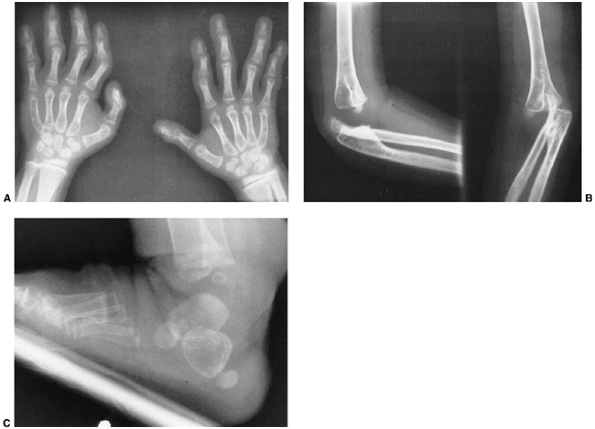

Figure 9.17 Nail-patella syndrome. The classic quartet of features consists of dystrophic nails (A), absent patellae (notice the region of osteochondritis dissecans on the lateral film) (B), posterior dislocation of the radial head (C), and iliac horns (D).

findings that include nail dysplasia, patellar hypoplasia, elbow

dysplasia, and iliac horns (183). The most prominent feature is dystrophic nails (Fig. 9.17A). The nail may be completely absent, hypoplastic, or have grooves and distortions in its surface (184).

common (Fig. 9.17B). An intraarticular septum makes arthroscopic management difficult, but the septum can be removed arthroscopically.

children, but may become symptomatic with time. In symptomatic

individuals, excision of the radial head will improve symptoms arising

from the prominent lateral bump, but the range of motion is rarely

improved. Although traditional teaching advocates performing radial

head excision after skeletal maturity, earlier excision in symptomatic

children does not seem to be associated with significant problems (185). Dislocated hips (195) and clubfeet can occur, and can be managed using techniques similar to those in idiopathic cases.